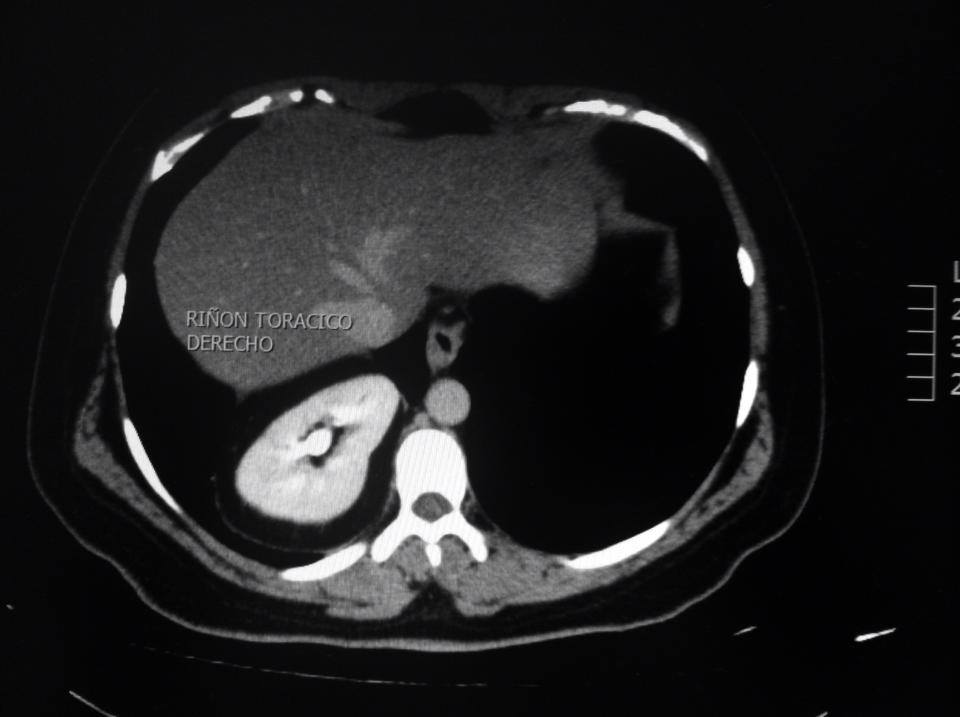

Tomografía que demuestra riñón ectópico torácico derecho